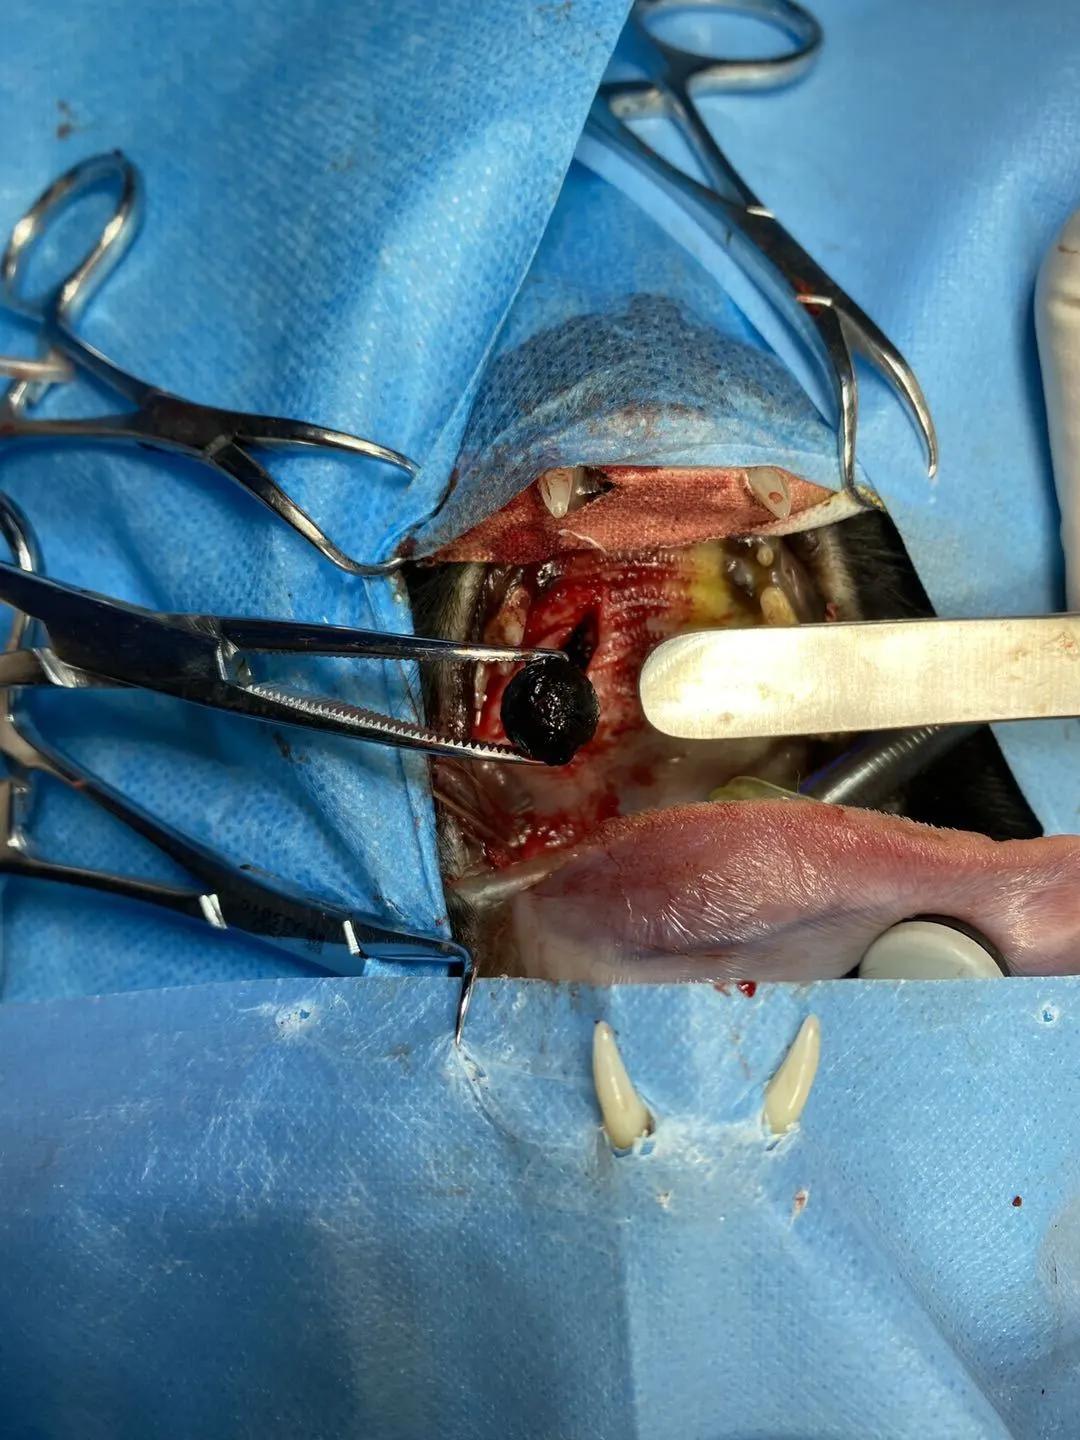

猫咪坨坨鼻腔异物,术前不能吞咽,影响进食,手术经口腔取出↓↓